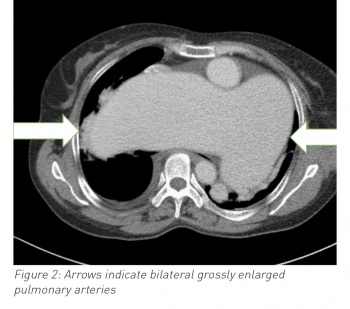

Blood work showed a neutrophilia, hypochromic anaemia, elevated C-reactive protein and an acidotic type two respiratory failure. A chest radiograph was significant for an opacity in the lower two-thirds of the left lung field and a second opacity in the right mid-zone. Given the woman’s past history the differential included right-sided pneumonia, left-sided pleural effusion and cardiomegaly, or hypertrophied pulmonary arteries.

A computed tomography scan confirmed grossly hypertrophied pulmonary vasculature.